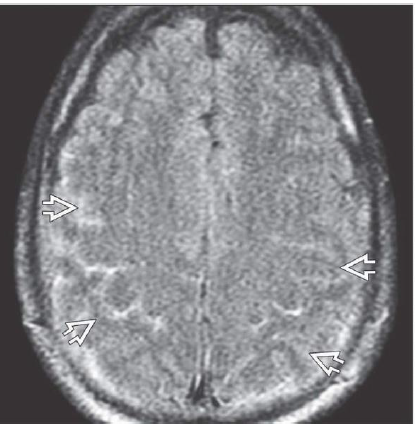

Findings of SDH on GRE and FLAIR

T2* GRE scan shows some “blooming” in the sSDH. 2-36C. DWI shows the classic “double layer”

appearance of an sSDH with hypointense rim on the inside and mildly hyperintense rim on the outside

of the clot